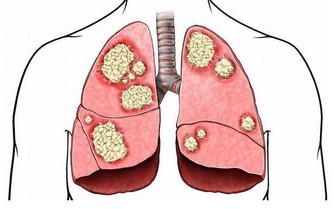

新興社會的到來,讓大家過上好日子了,同時,也讓很多人養成了大量的惡習,在眾多惡習之下,很容易引發一些問題,幽門螺桿菌感染率變高,就是其中一個問題。人體內有很多菌群,有些是有益菌,有些是不好的細菌,幽門螺桿菌就是一個極壞的細菌,對胃黏膜造成的損傷也很大,且攻擊性極強,繁殖力也很厲害,不及時的治療,就可能誘發癌症。

但不得不說,多數被感染的人群,都是需要治療的,因為胃部情況並不良好,對於已經出現消化性潰瘍和慢性胃炎的人,或者說家裡有過胃癌病史的人,還是需要及時進行治療的,以免給胃部帶來更大的傷害。